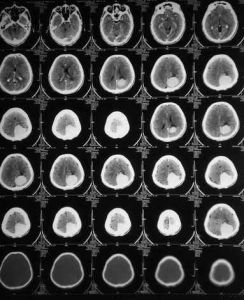

(3).腦ET

(6).單光子反射計算機斷層顯像檢查

利用MED---經顱腦神經遞質檢測技術,區別於傳統單一的檢測方法,整合了FC—腦漲落圖儀、傳統腦神經遞質檢測設備、DNR—多尼爾超導檢測、腦ET、核磁共振、單光子反射計算機斷層顯像等多種檢測手段,利用儀器對人體大腦神經遞質信號的監測,

深層採集人腦三大神經元內標物以及15種中樞神經遞質:包括氮-乙醯天門冬氨酸複合物(N-acetylaspartate,NAA)、膽鹼複合物(Cholin,Cho)和肌酸-磷酸肌酸複合物(Creatin,Cr),以及γ-氨基丁酸(GABA)、谷氨酸(Glu)、5-羥色胺(5-HT)、乙醯膽鹼(Ach)、去甲腎上腺素(NE)、多巴胺(DA)等,充分記錄其功能現狀數據以及綜合活躍程度,同時分析腦部物理損傷及神經元病變參數,並依此製成數位化報告,提交給經驗豐富的精神疾病專家。

濟南五洲醫院精神科再由精神疾病專家根據可視化報告中的腦內神經遞質形態圖譜對患者的病況病狀信息進行科學分析,進而迅速精準的診斷出患者的腦功能活動情況,判斷其病患神經元的位置、受損狀況、還有病變程度,由此結論出患者的病因病灶,確定其治療方法及治療基調。

(2)由於精神疾病的發生與多種腦部疾病有關,以往的CT、核磁共振等檢查技術只能檢測大腦的形態學變化,但多數患者的大腦沒有明顯的形態學方面的改變,因此這就使得臨床心理障礙的治療缺少針對性,導致療效不佳,而MED---經顱腦神經遞質檢測,僅僅需要6分鐘就可以完整採集人體的腦神經遞質信號,並據此建立起配體與受體互相作用的一整套數字依據,在精準定位大腦中受損的腦細胞的同時,迅速診斷出其導致病症的病灶病因,為醫務人員提供腦內神經細胞活動的具體情況,為病症的診斷及治療提供了有效的依據。